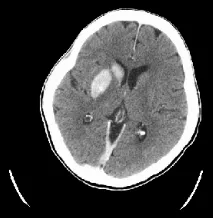

患者在发病80分钟时完成CT平扫,显示右侧颈动脉及大脑中动脉(MCA)M1段、M2段高密度征,提示血栓非常长;ASPECTS评分10分。

术后即刻CT,发现造影剂部分外渗。

24小时复扫CT,造影剂外渗完全消失。